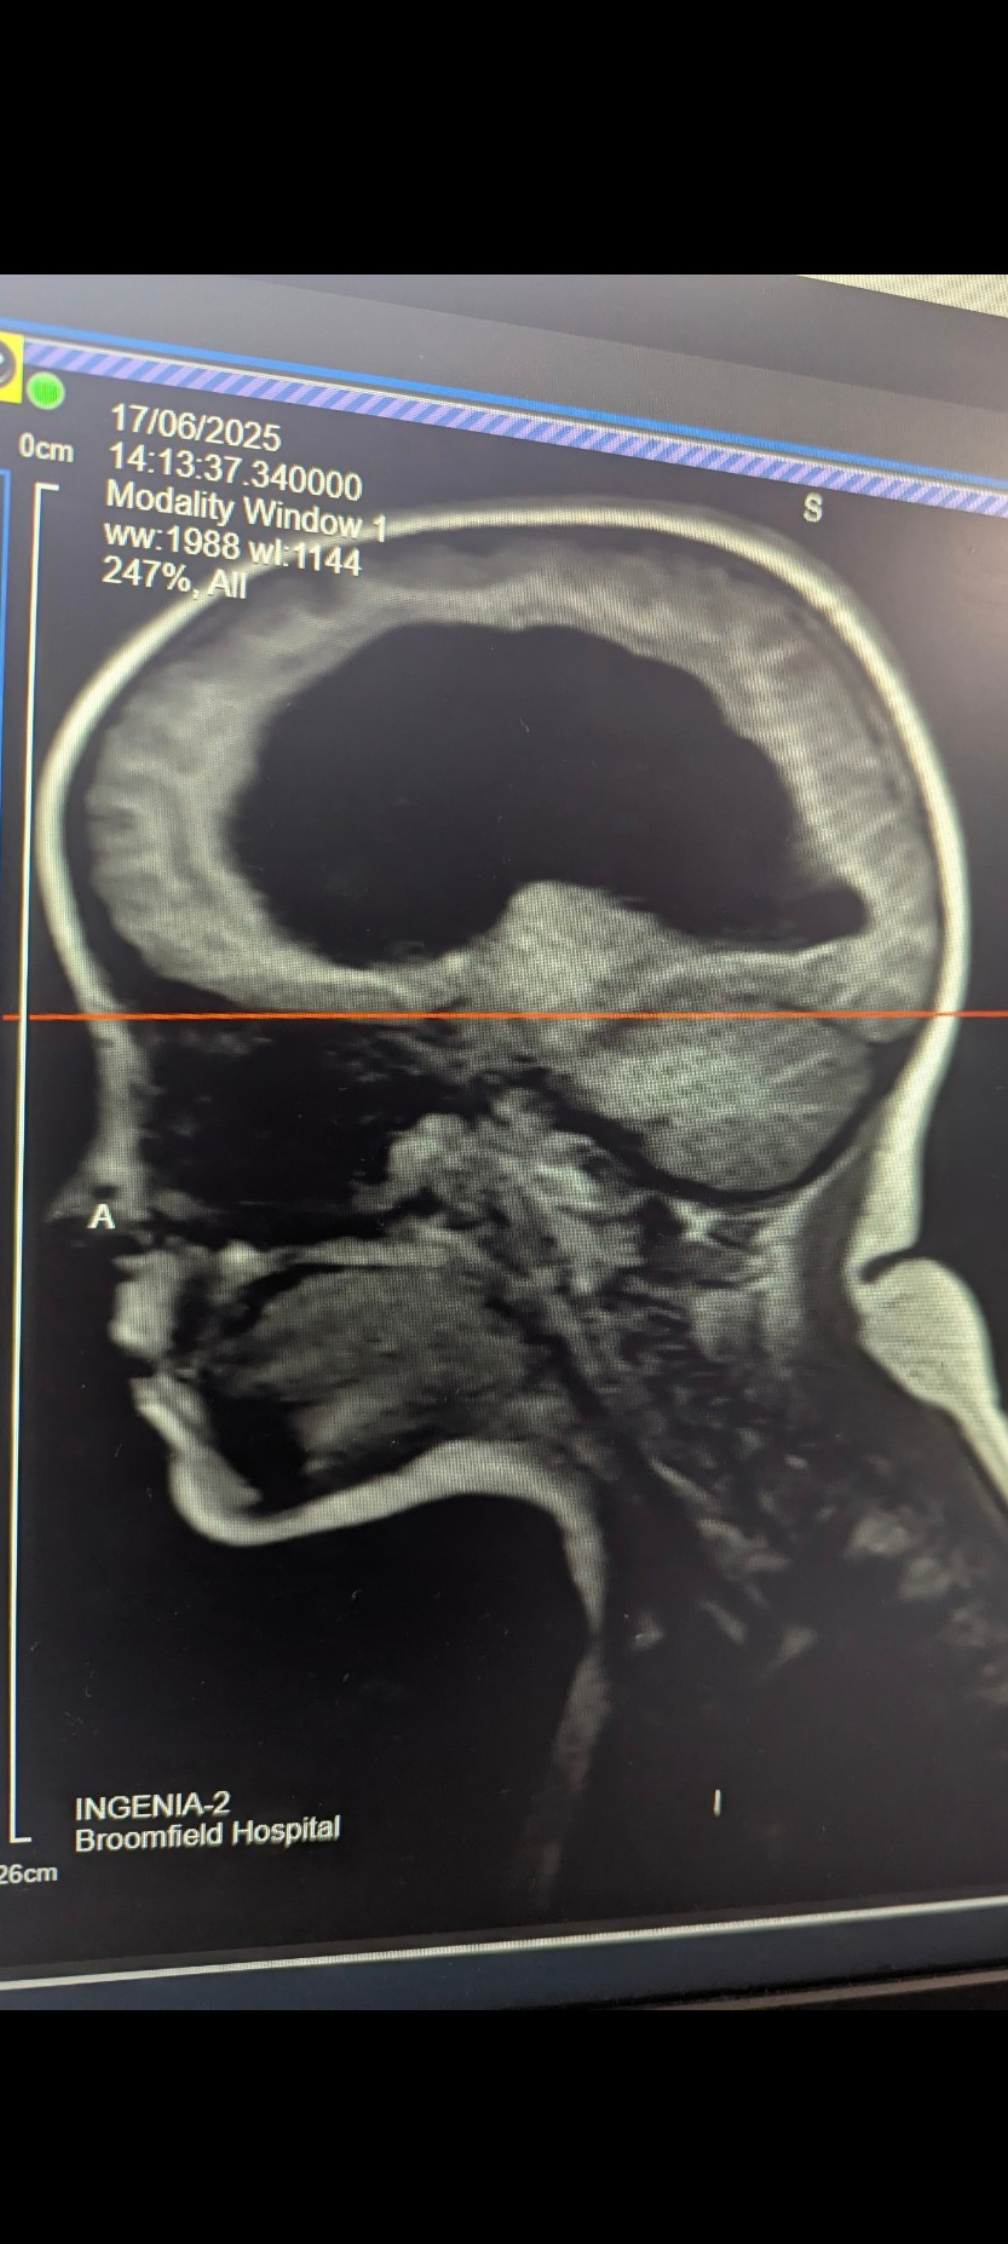

After being referred back to the hospital by the optician who had diagnosed Lola with papilledema (swelling of the optic nerve) Lola had an emergency MRI scan the following day. This revealed Lola had a tumor on the tectal plate of her brain causing a condition called obstructive hydrocephalus (a blockage causing build of cerebral spinal fluid in the brain) this was creating severe intracranial pressure and I was told she would need surgery immediately. We were transferred to great ormand street hospital by ambulance that night.

Once Lola was settled a nurse stayed with her to allow me to have a discussion with a neuro surgeon who expressed to me the severity of lolas condition. She explained that it was by miracle that Lola was walking and talking and that she had not had worse symptoms with her eyesight. When I expressed that she would have been having a scan in 6-8 weeks following referral by our GP the surgeon told me she would not have survived. Lola was extremely lucky that she had not experienced worse and potentially fatal symptoms considering the amount of pressure in her brain (MRI scan showing the amount of CSF build up in brain is in photo gallery) the surgeon talked me through the procedure (Endoscopic third ventriculostomy) they would be performing on Lola the following morning. This procedure was to open the ventricle and allow the fluid to drain and decrease the pressure in Lola's brain. They also would be attempting to take a biopsy of the tumor.